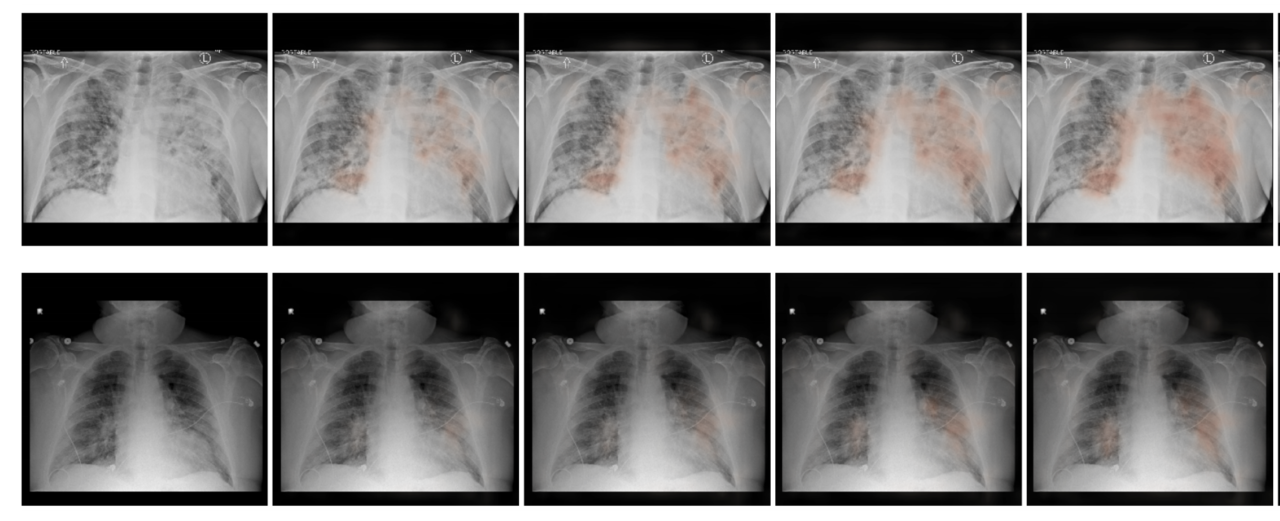

We processed the chest X-ray images using the Globally Aware Multiple Instance Classifier (GMIC) neural network architecture [1]. COVID-GMIC predicts the overall risk of deterioration within 24, 48, 72, and 96 hours, and computes saliency maps that highlight the regions of the image that most informed its predictions. As shown in Figure 2, COVID-GMIC utilizes the global network to generate four saliency maps that highlight the regions on the X-ray image that are predictive of the onset of adverse events within the four time windows. COVID-GMIC then applies a local network to extract fine-grained visual details from these regions. Finally, it employs a fusion module that aggregates information from both the global context and local details to make a holistic diagnosis. The predictions of COVID-GMIC are combined with predictions of a gradient boosting model [2] that learns from routinely collected clinical variables, referred to as COVID-GBM. The optimal weights assigned to the COVID-GMIC prediction in the COVID-GMIC and COVID-GBM ensemble were derived through optimizing the performance on the validation set (obtained from the folds of the Monte Carlo cross validation iterations).

Interpretability to establish trust with clinicians

We also qualitatively evaluated the saliency maps computed by COVID-GMIC. Two examples are shown in Figure 3. Both patients were admitted to the intensive care unit and were intubated within 48 hours. In the first example, there are diffuse airspace opacities, though the saliency maps primarily highlight the medial right basilar and peripheral left basilar opacities. Similarly, the two regions of interest (ROI) patches (1 and 2) on the basilar region demonstrate comparable attention values, 0.49 and 0.46 respectively. In the second example, the extensive left mid to upper-lung abnormality (ROI patch 1) is highlighted, which correlates with the most extensive area of parenchymal consolidation.

Figure 3: From left to right: the original X-ray image, saliency maps for clinical deterioration within 24, 48, 72, and 96 hours, locations of region-of-interest (ROI) patches, and ROI patches with their associated attention scores.